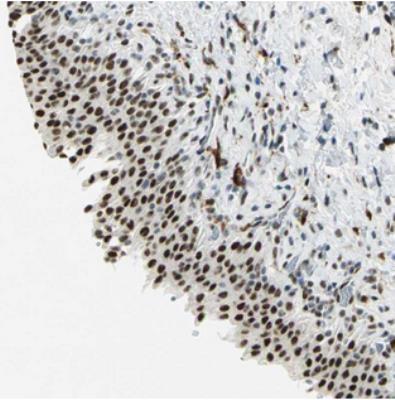

- Rabbit Polyclonal Myotubularin Related Protein 10 Antibody

- Immunohistochemistry: Myotubularin Related Protein 10 Antibody [NBP2-30553] - Staining of human urinary bladder shows strong nuclear positivity in urothelial cells.